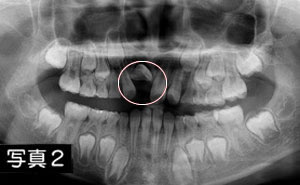

そのレントゲン写真にて、右前歯が横を向いているのが分かります。【写真2】